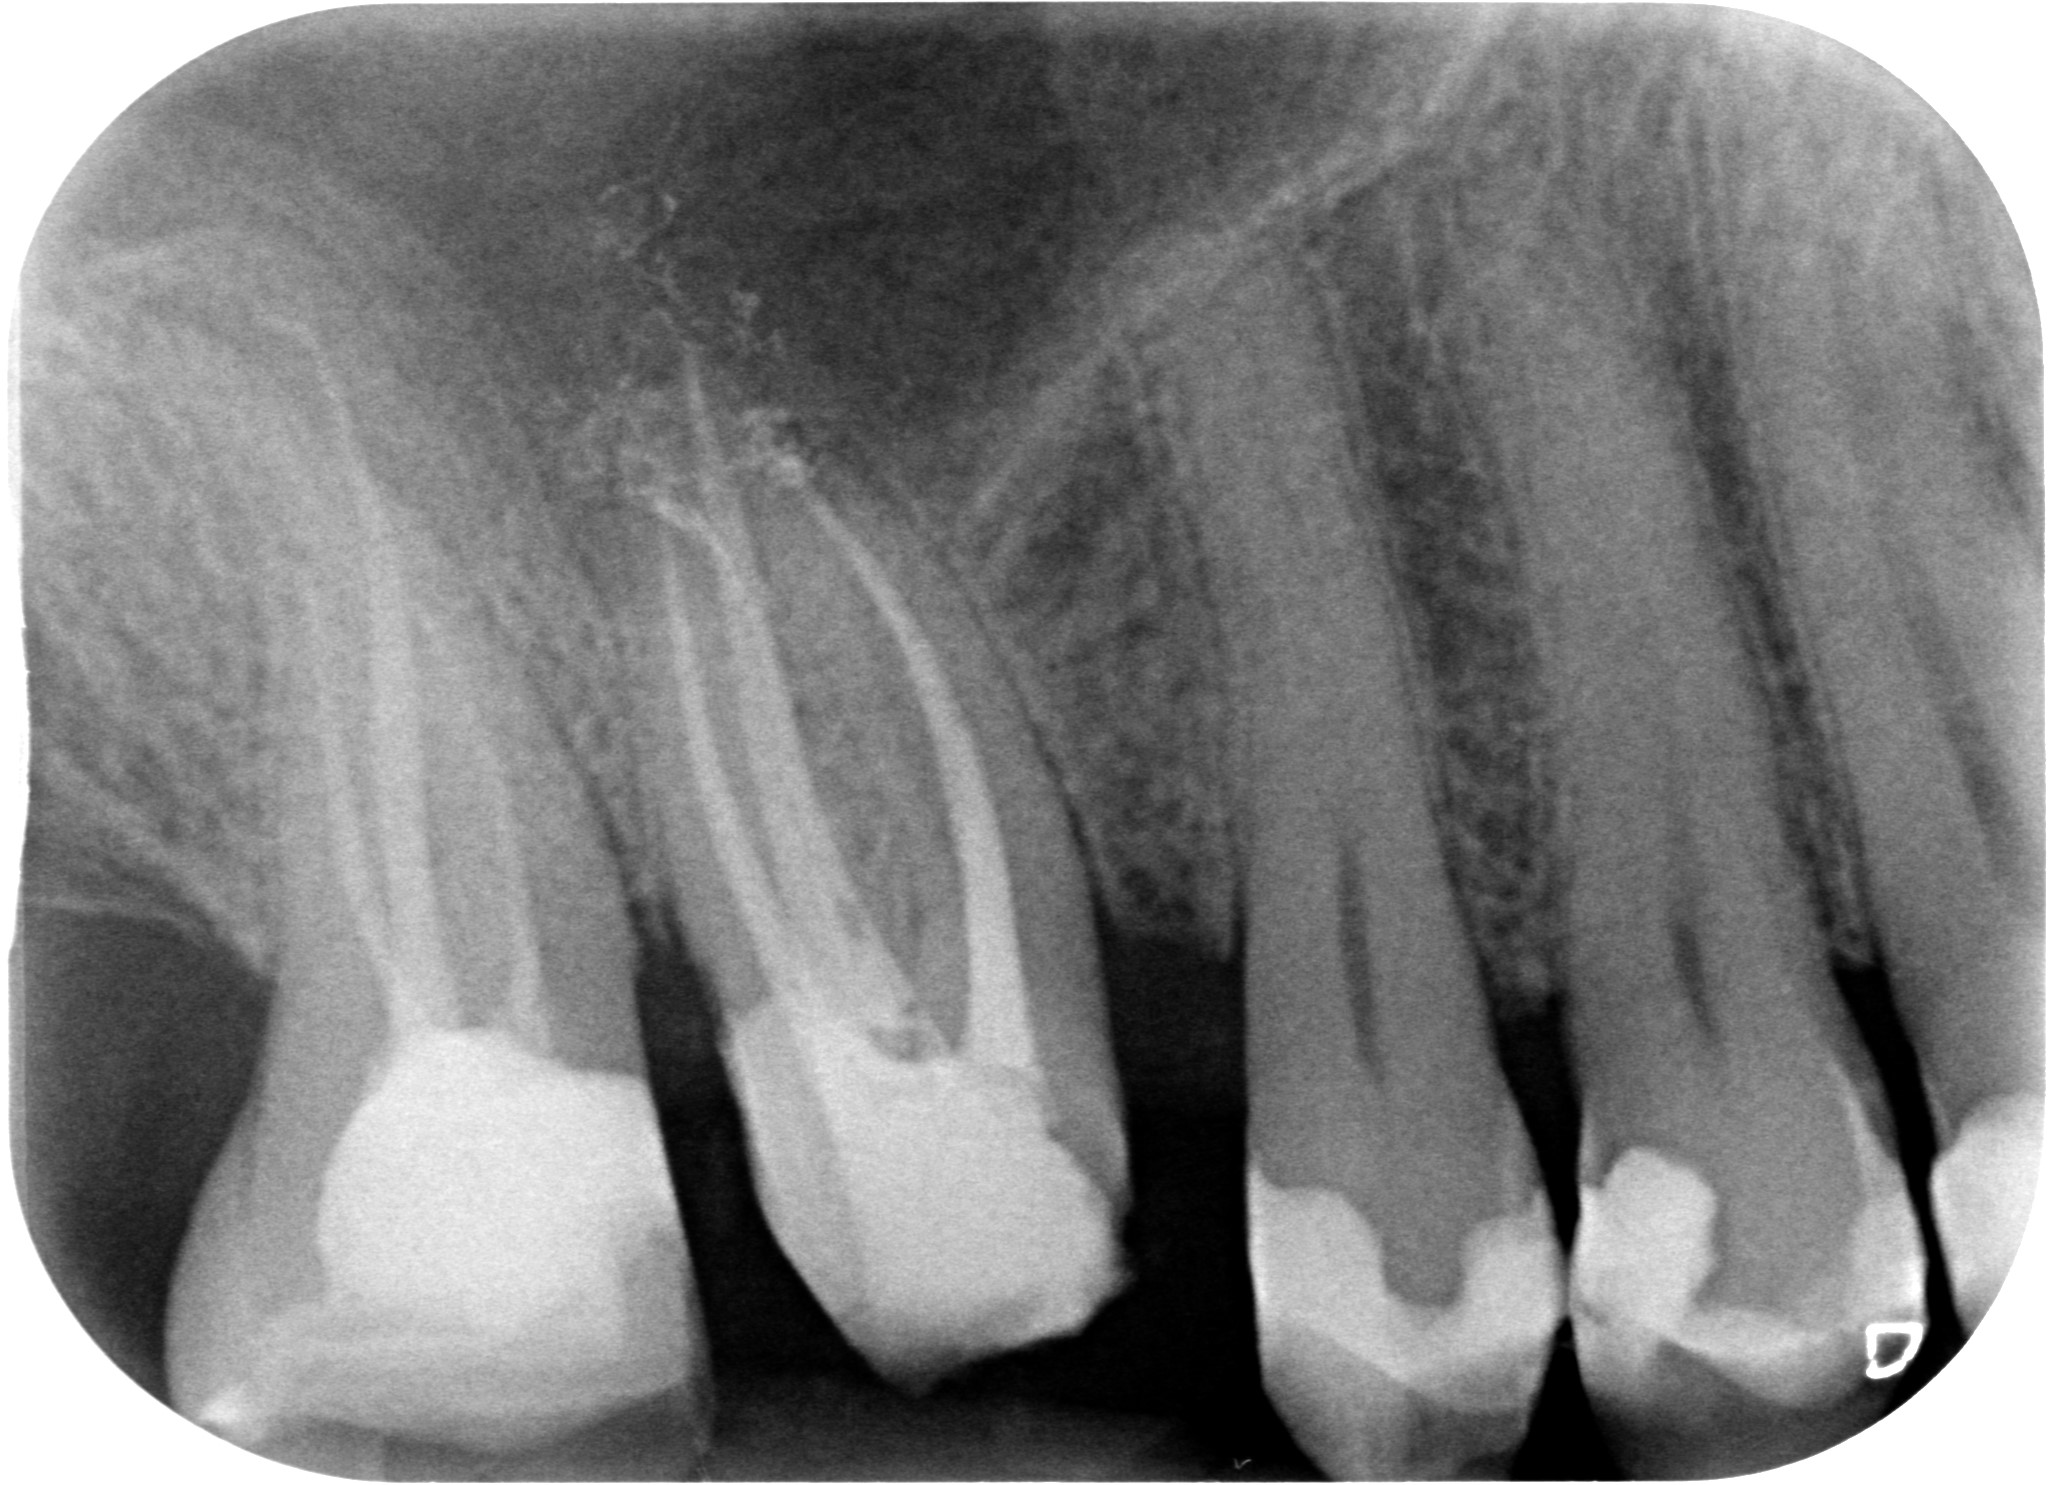

Il riposizionamento apicale dei tessuti parodontali ci consentirà quindi di:

ESEGUIRE UN CORRETTO PRETRATTAMENTO CORONALE

ESEGUIRE UN CORRETTO RITRATTAMENTO CANALARE ISOLANDO IL CAMPO CON LA DIGA DI GOMMA

ESEGURE UN CORRETTO RESTAURO PROTESICO